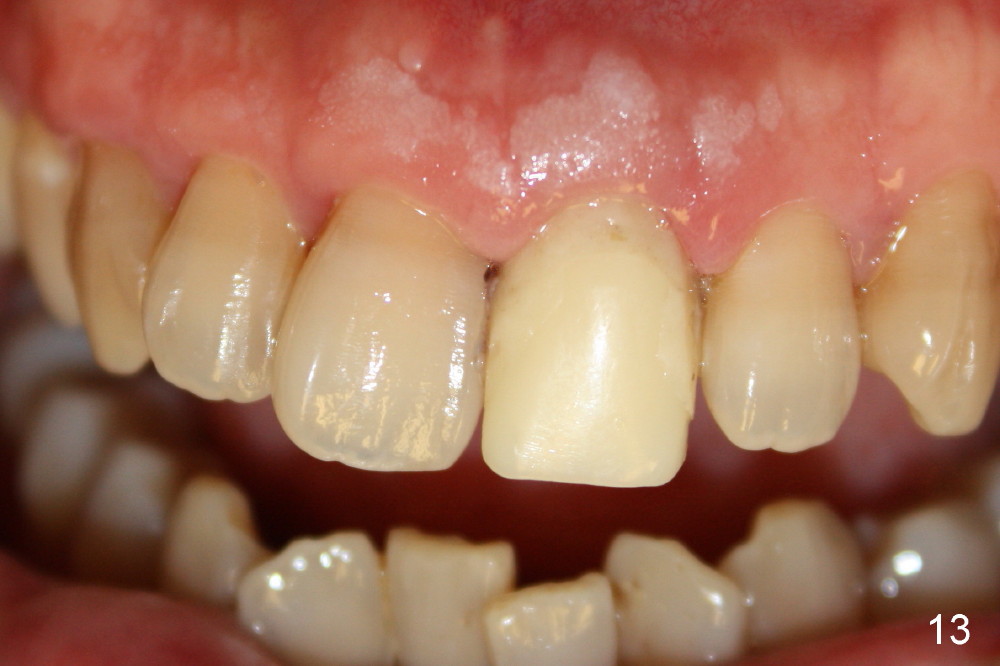

Bone expansion allows the implant (Fig.9 I) to have primary stability (insertion torque between 50 and 60 Ncm), since the cortex of the incisive canal is apparently intact.  Allograft is placed in the labial gap (Fig.10, 11 *) following installation of the abutment (A).  Finally an immediate provisional (Fig.10,12 P) is cemented.  Fig.13,14 are taken 8 days postop.  The patient returns 3 months postop (Fig.15,16).  Osteointegration appears to have occurred (Fig.15 arrowheads) and is more obvious 9 months postop (Fig.17).